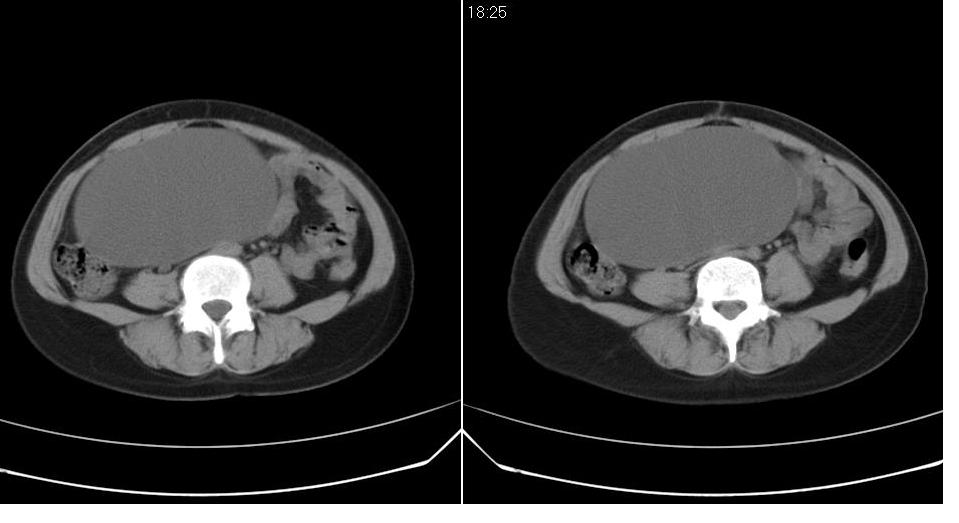

女 35岁,下腹部坠感疼,其它病史不详。图象顺序有点乱。

定位于盆腔附件,有囊性密度,有脂肪密度、还有骨密度;应该是比较典型的卵巢畸胎瘤。